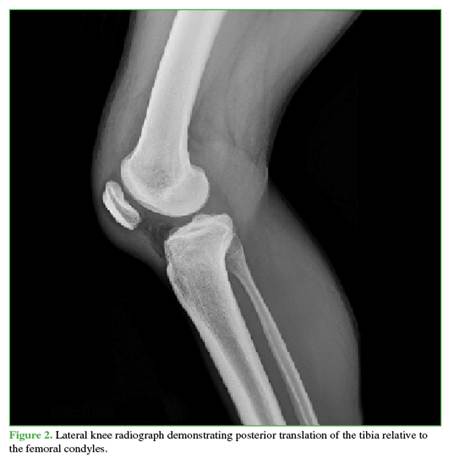

A 27-year-old male farmer residing in a rural area, with no relevant medical history, suffered a traffic accident after falling into a ravine while riding a motorcycle, resulting in trauma to his right shoulder and knee. He initially sought care at a rural hospital, where marked edema, ecchymosis, and a positive dimple sign were identified in the right knee. He also had limited range of motion in both the shoulder and the knee. As X-rays were not available, he was referred to a hospital with orthopedic services. There, initial radiographs were obtained (Figures 1 and 2), documenting a diaphyseal humeral fracture that was immobilized with a sugartong splint. In addition, a posterolateral knee dislocation and a lateral patellar dislocation were diagnosed. Two orthopedic surgeons attempted three reductions under sedation (no anesthesia was available), successfully reducing the patella but not the knee. It was decided that the patient required transfer to a trauma center for urgent open reduction and to rule out an associated vascular injury. The knee was immobilized with a bivalved hip-to-foot splint and he was referred.

Radiographs showed widening of the medial joint space consistent with medial instability. Further imaging was obtained with magnetic resonance imaging (Figures 4 and 5) to evaluate possible interposed tissues or structures, and with CT angiography (Figure 6) to rule out vascular injury given the time elapsed since trauma. Marked edema was noted in the medial soft tissues, including the capsule and medial structures in the intercondylar region, along with persistent knee subluxation. Vascular compromise was ruled out, with preservation of the femoropopliteal vascular bundle.